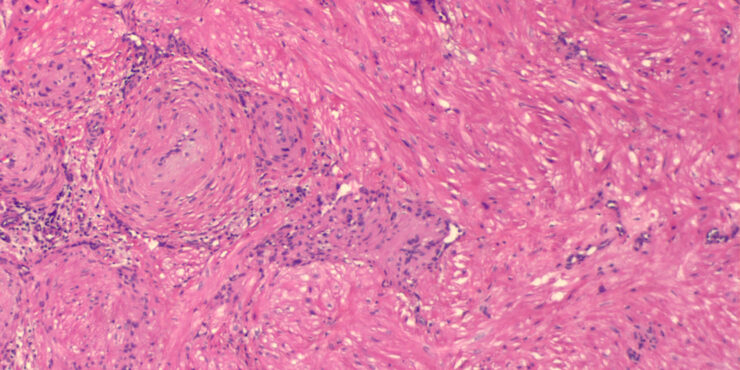

Read MoreAlopecia mucinosa = الحاصة المخاطينية Alopecia Mucinosa Follicular mucinosis is characterized clinically by grouped erythematous papules and/or plaques that may be markedly indurated or nodular ( and histologically by mucin accumulation in hair follicles . It can be classified into two types: a primary (idiopathic) type and a secondary variety. The primary form tends to have a […]